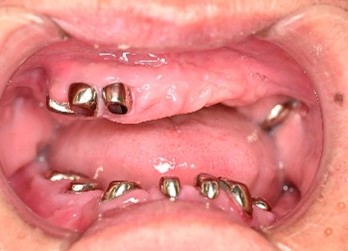

Before

赤丸は抜歯しました

After

【義歯を装着したところ】

【義歯を外したところ】

マグネット式総入れ歯

緑丸は組み込まれたマグネット